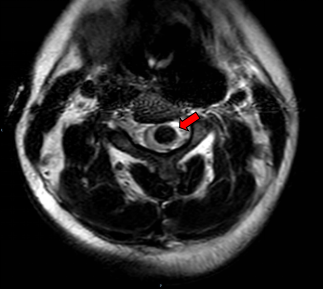

术前MRI提示C3-4髓内占位并破裂出血

患者李女士(化名)是一位38岁的高龄孕妇。孕38周+2天时,她突然出现左侧肢体无力、麻木,症状迅速加重,经过紧急检查,医生发现她颈部脊髓的第3节段有出血,并伴有明显的水肿。最终,她被诊断为颈3-4节段脊髓动静脉畸形并出血。